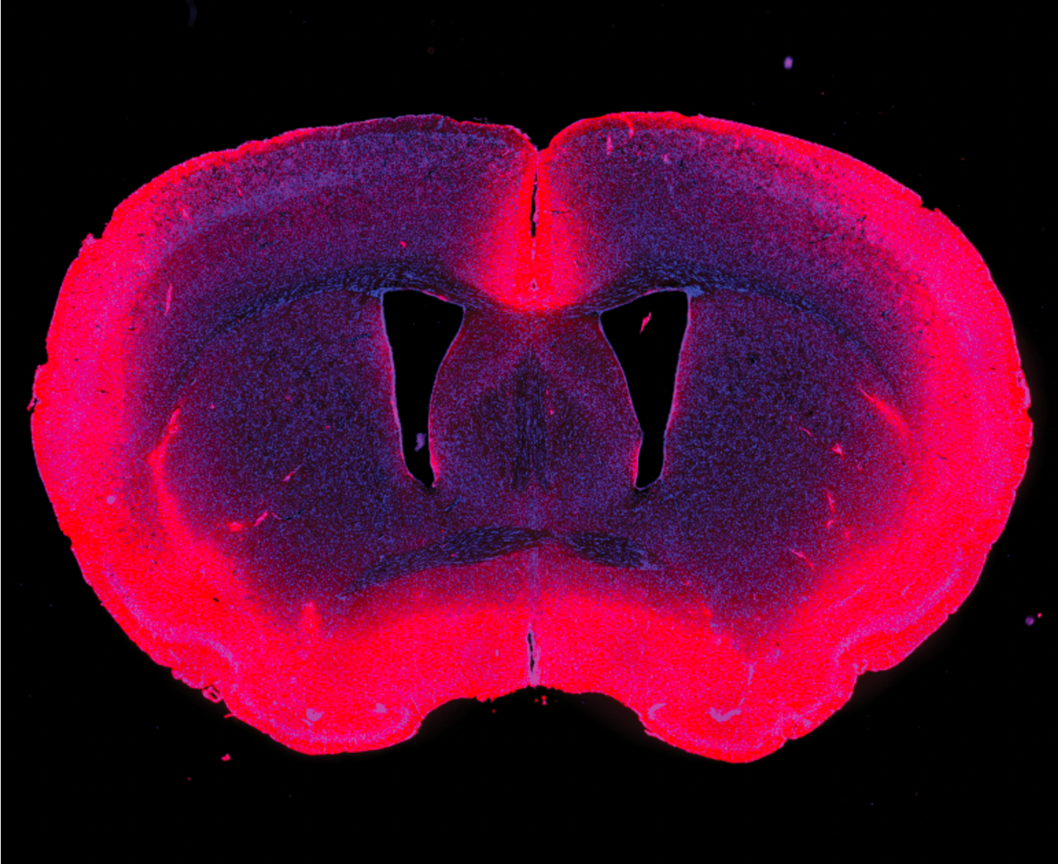

Her research focuses on the glymphatic system, a brain-wide network of perivascular pathways and aquaporin-4 (AQP4) water channels, that facilitates the exchange of fluid throughout the brain and is important for the transportation and clearance of solutes and brain waste. Glymphatic system dysfunction occurs in normal aging as well as many neurological disorders, such as Alzheimer's disease, Parkinson’s disease, stroke, traumatic brain injury, and cerebral small vessel disease.

Current projects in the lab are examining neutrophil extracellular trap-induced glymphatic dysfunction in Alzheimer’s disease and menopause-induced glymphatic dysfunction as a possible risk-factor for Alzheimer’s disease. The Braun lab is also examining differences in localization of AQP4 water channels across mammalian species with varying levels of cortical folding and how this may impact glymphatic function.

During her postdoctoral work, Dr. Braun examined how loss of perivascular aquaporin-4 (AQP4) localization impaired glymphatic function and promoted amyloid pathology, using both human post-mortem brain tissue and a double transgenic mouse model (Alzheimer’s Res Ther 2022). She also examined how AQP4 mislocalization impairs glymphatic clearance of alpha-synuclein (bioRxiv 2024) and tau pathology (in prep). Current projects in the Braun lab are continuing in this line of investigation, examining mechanisms of glymphatic dysfunction in Alzheimer’s disease.